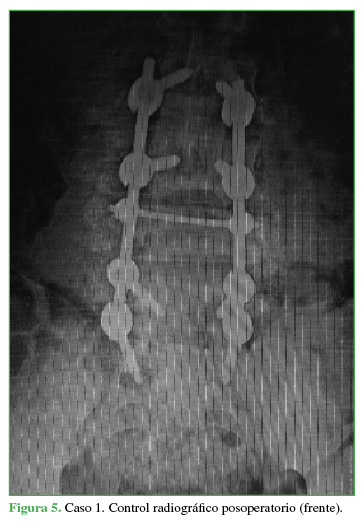

PropiaSe decide efectuar una cirugía con abordaje posterior lumbosacro, descompresión posterolateral directa por técnica de tipo eggshell, con resección del arco posterior de L4 y reducción de los fragmentos en retropulsión.25-27 Se realiza artrodesis lumbosacra larga L2-S1 (Figuras 4 y 5).

El paciente evoluciona favorablemente con cicatrización de la herida quirúrgica. Comienza con rehabilitación en el posoperatorio inmediato. Se corrige la cifosis segmentaria con medición radiográfica a los seis meses de la cirugía adecuada (Cobb L3-L5 33°, lordosis lumbar 44°, incidencia pelviana 44°, IP-LL 0°, inclinación de la pelvis 18°). El paciente recupera la sensibilidad por completo y evoluciona con una secuela deficitaria parcial motora de raíz L4 izquierda, extensión activa del pie grado 3 (vence gravedad). La TC de control a los dos años muestra la consolidación (Figura 6). Vuelve a montar a caballo (Figura 7 y video ).